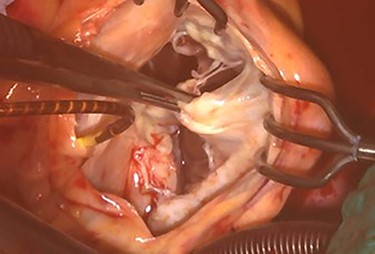

At his 1-year follow-up visit, the patient presented with shortness of breath on exertion and leg edema; thus, we decided to perform surgical correction. After median sternotomy, cardiopulmonary bypass was established with ascending aortic and bicaval venous cannulations. MyoPore (Greatbatch Medical, NY, USA) bipolar sutureless screw-in lead was attached to the left ventricle. A permanent PM was implanted, and left atrial appendage exclusion with AtriClip (AtriCure, OH, USA) was performed afterward. A right atriotomy was performed to facilitate exposure, wherein we found that the septal and posterior leaflets of the tricuspid valve were severely damaged (Fig. 3). Micra was placed over the right ventricular septum and was easily freed under direct vision (Fig. 4). After the leaflets were excised, an Epic (St Jude Medical, MN, USA) 33-mm bioprosthesis was implanted.

Intraoperative photograph; Micra was retrieved under direct vision.